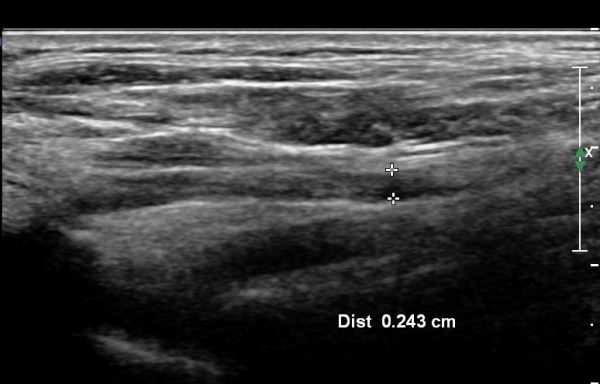

ÃÊÀ½ÆÄ °Ë»ç :  ÁÂÃø ¸ñ ¾Õ ¿ÜÃø¿¡¼­ °üÂûÇÑ Á¦5°æÃß ½Å°æ±Ù Ⱦ´Ü¸é°Ë»ç¿¡¼­ Á¦5°æÃß ½Å°æ±ÙÀÇ °æ¹ÌÇÑ Àú¿¡ÄÚ

ºÎÁ¾ÀÌ °üÂûµÊ(»çÁø 1).